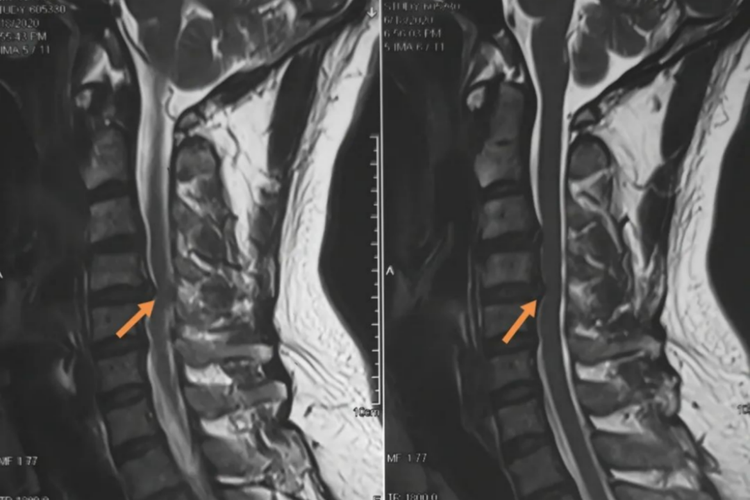

颈椎间盘突出症是由颈部创伤、退行性病变等因素导致。本病多见于青壮年,男性多于女性,对于颈椎管矢状径较宽者,发病年龄可偏大。

颈椎间盘变性、压缩、纤维环破裂及髓核脱出,刺激压迫颈椎动脉、脊神经、脊髓等,引起头痛、眩、心悸、颈部酸胀、活动受限、肩背部疼痛、上肢麻木胀痛、四肢无力等症状,严重时可能会发生高位截瘫危及生命。